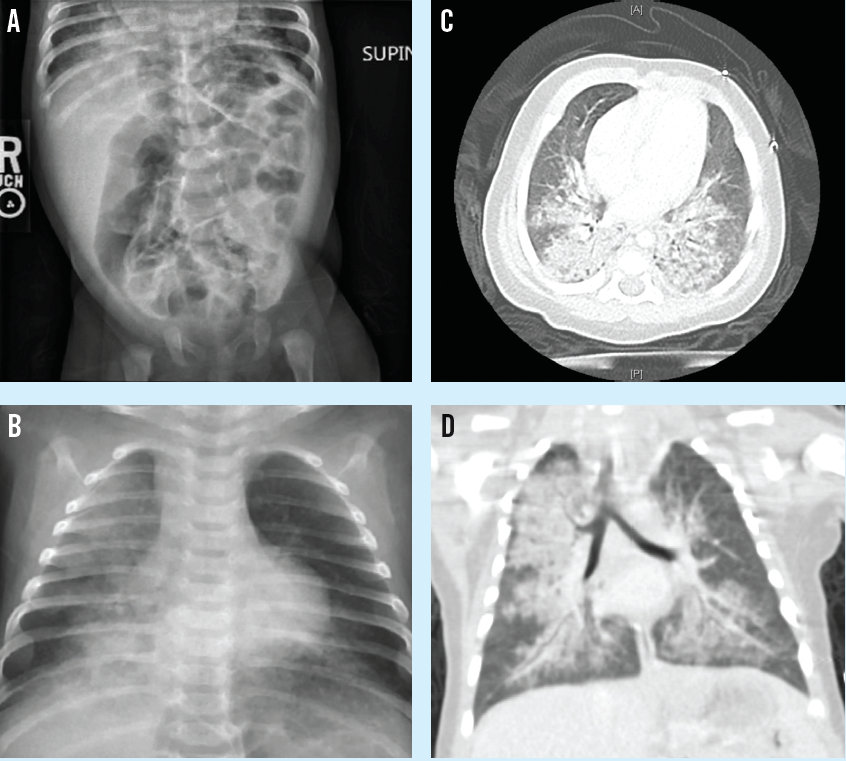

Julie S. Berg, MD; Neha H. Shah, MD, MPH

A 5-year-old boy presented to the emergency department with a 1-month history of cough that had been unresponsive to albuterol.

01/21/2020